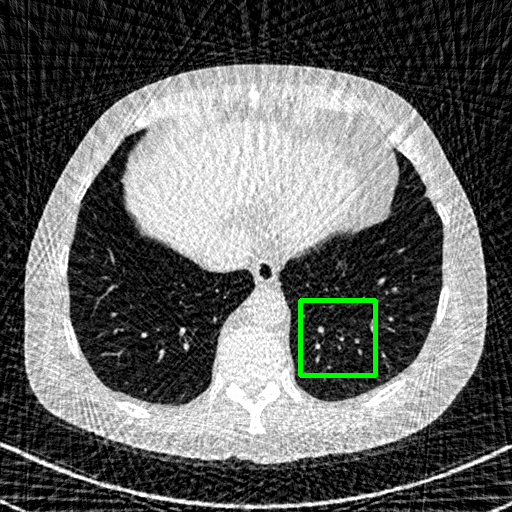

Generalizablity on COVID-19 dataset. Finally, we use slices of another patient in the COVID-19 dataset to test the generalizability of trained models, and quantitative performances are compared in Table 4. ImgTrans and DuDoTrans have achieved a larger improvement about 4-5 dB over CNN-based methods, which shows that the long-range dependency modeling ability helps capture the intrinsic global property of general CT images. Further, our DuDoTrans exceeds ImgTrans about 0.4 dB in all cases, even larger than the original NIH-AAPM dataset. The improvement ensures that DuDoTrans generalizes well to out-of-distribution CT images. Besides, we also show the visualization images in Fig. 5 when = 96. Coinciding with the quantitative comparison, our DuDoTrans show better reconstruction on both global patterns and local details.

Ground Truth

FBP

FBPConvNet

DuDoNet

ImgTrans

DuDoTrans